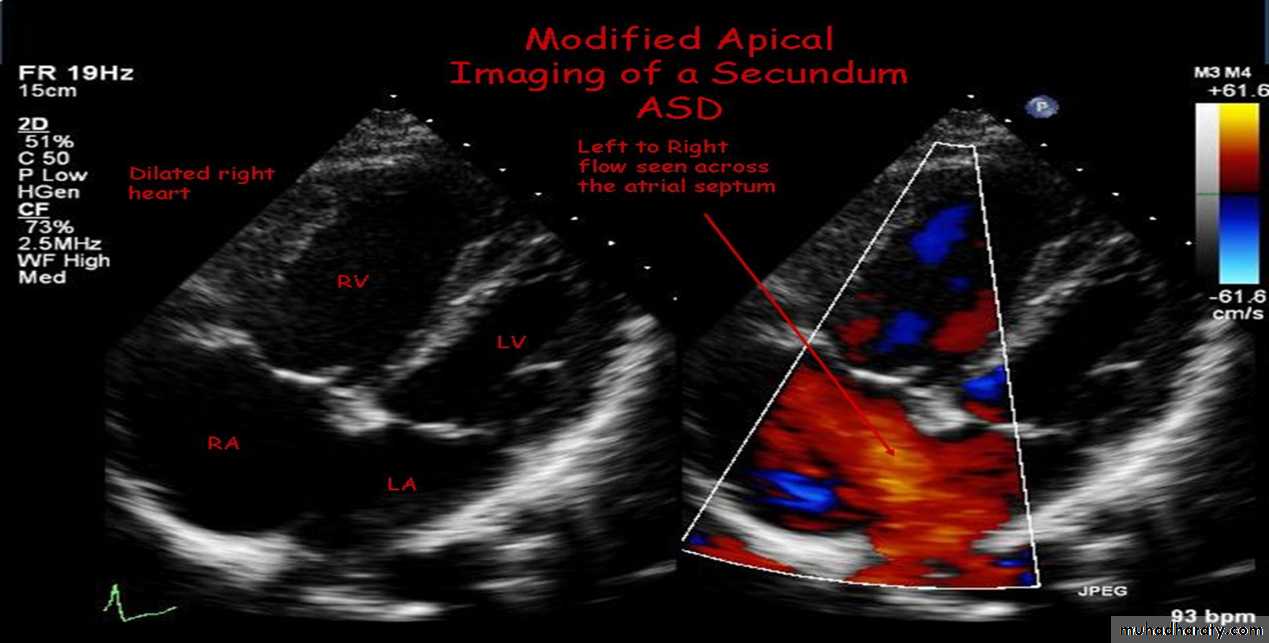

3-Echocardiography

Congenital heart disease

The location and size of the atrial defect are readily appreciated by two-dimensional scanning . The shunt is confirmed by pulsed and color flow Doppler .